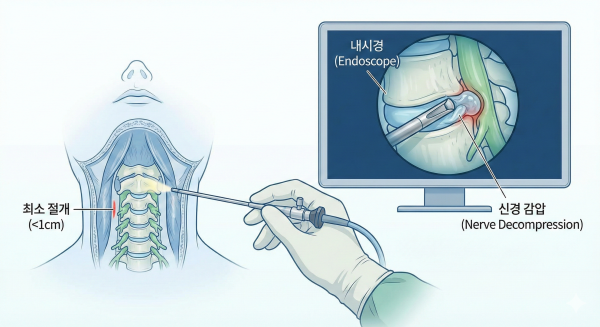

경추내시경감압술이 효과적인 대안이 됩니다.

이 치료법은 약 1cm 미만의 최소 절개를 통해 내시경으로 병변 부위만 정밀하게 제거합니다.

경추내시경감압술의 장점

정상 조직 손상이 거의 없어 수술 후 통증이 적음.

하루 이틀 정도의 입원 후 바로 일상생활 복귀 가능.

고령자나 만성질환자도 비교적 안전하게 시행 가능.